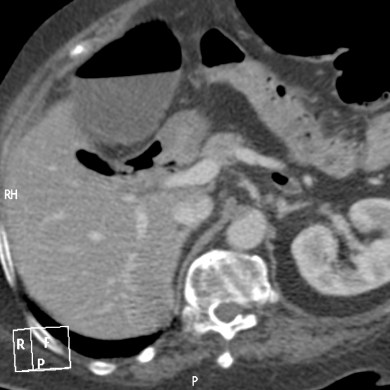

Se realiza un TC abdominal sin contraste:

Observar como posterior a la litiasis hay un cambio de calibre, el segmento que queda de ileon y el colon no están distendidos.

No encontramos ante un Ileo biliar, una obstucción intestinal mecánica ocasionada por una litaisis enclavada en el íleon terminal. La paciente estaba colecistectomizada, por tanto, lo más probable es que haya sido producido por una litiasis residual que pasó desapercibida.

- Dilatación por obstrucción de asas de delgado.

- Aerobilia.

- Litiasis (2 – 3 cm aprox). Hay que tener cuidado ya que muchas litiasis no están calcificadas y su densidad puede ser similar al contenido del intestino. Pueden ser multiples, por tanto hay que poner atención para que no pasen desapercibidas y evitar las recidivas.

- Fistulas (normalmente entre vesícula y duodeno)